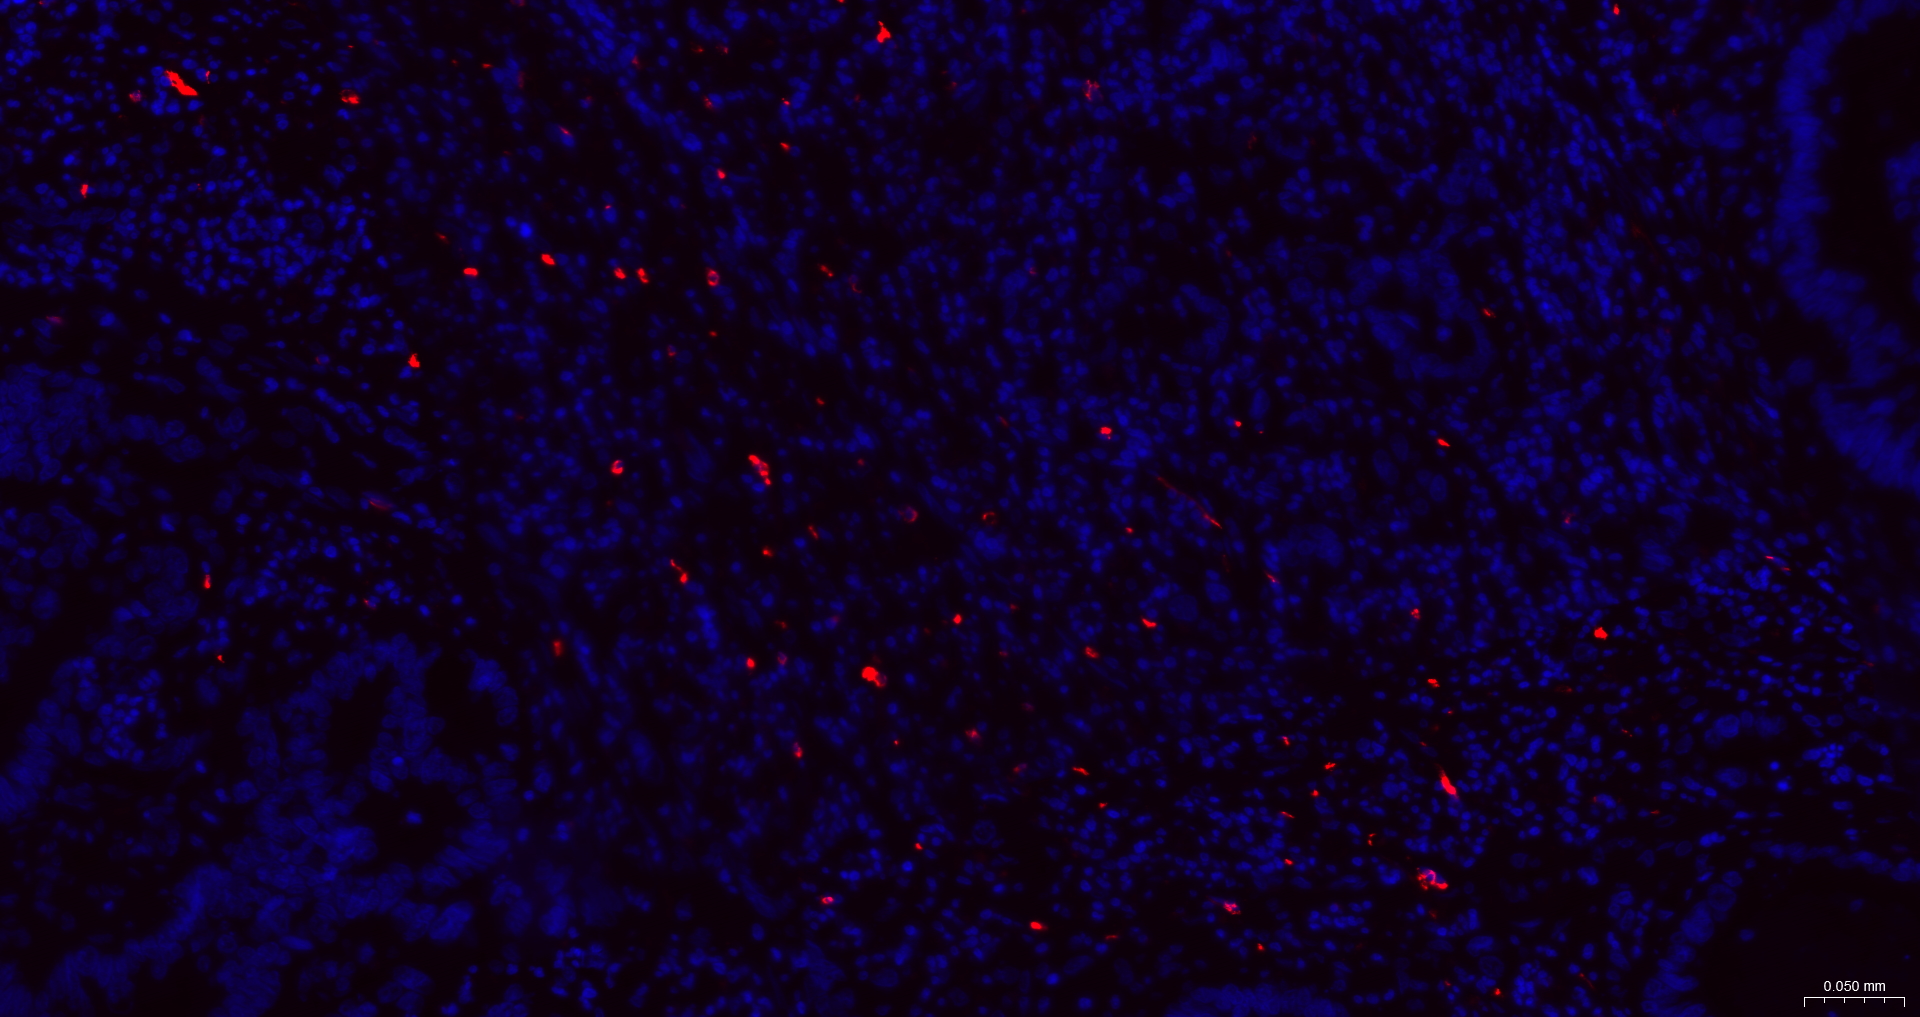

• IF(IHC-P)

IF(IHC-P) IFIHC-P1:50-200